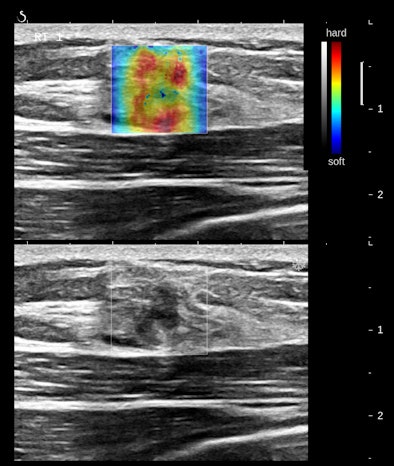

Figures 2A and 2B are cropped B-mode and simultaneous SWE of an 8-mm nodule in an isolated island of parenchyma in the upper outer quadrant of a 43-year-old woman.

| Figures 2A and 2B. |

The B-mode features are very abnormal, at the least BI-RADS 4. The elastogram is particularly interesting because the most abnormal area is the halo surrounding the small, peculiarly shaped nodule. This is the desmoplastic border of hard fibrous tissue that the body is erecting to delay tumor expansion. One might infer from this that this tumor has invasive features that are not apparent in the B-mode image. The pathology was microinvasive ductal carcinoma.

The principal determinants of elasticity that are mapped by shear-wave elastography appear to be cell density, interstitial pressure, and fibrosis. Very vascular nodules contribute both increased collagen from vessel walls and interstitial pressure from circulating blood. The important consideration is that these determinants of elasticity are cellular, below the level of resolution of B-mode imaging. SWE would appear to have the potential to reveal some cellular features of tissues.